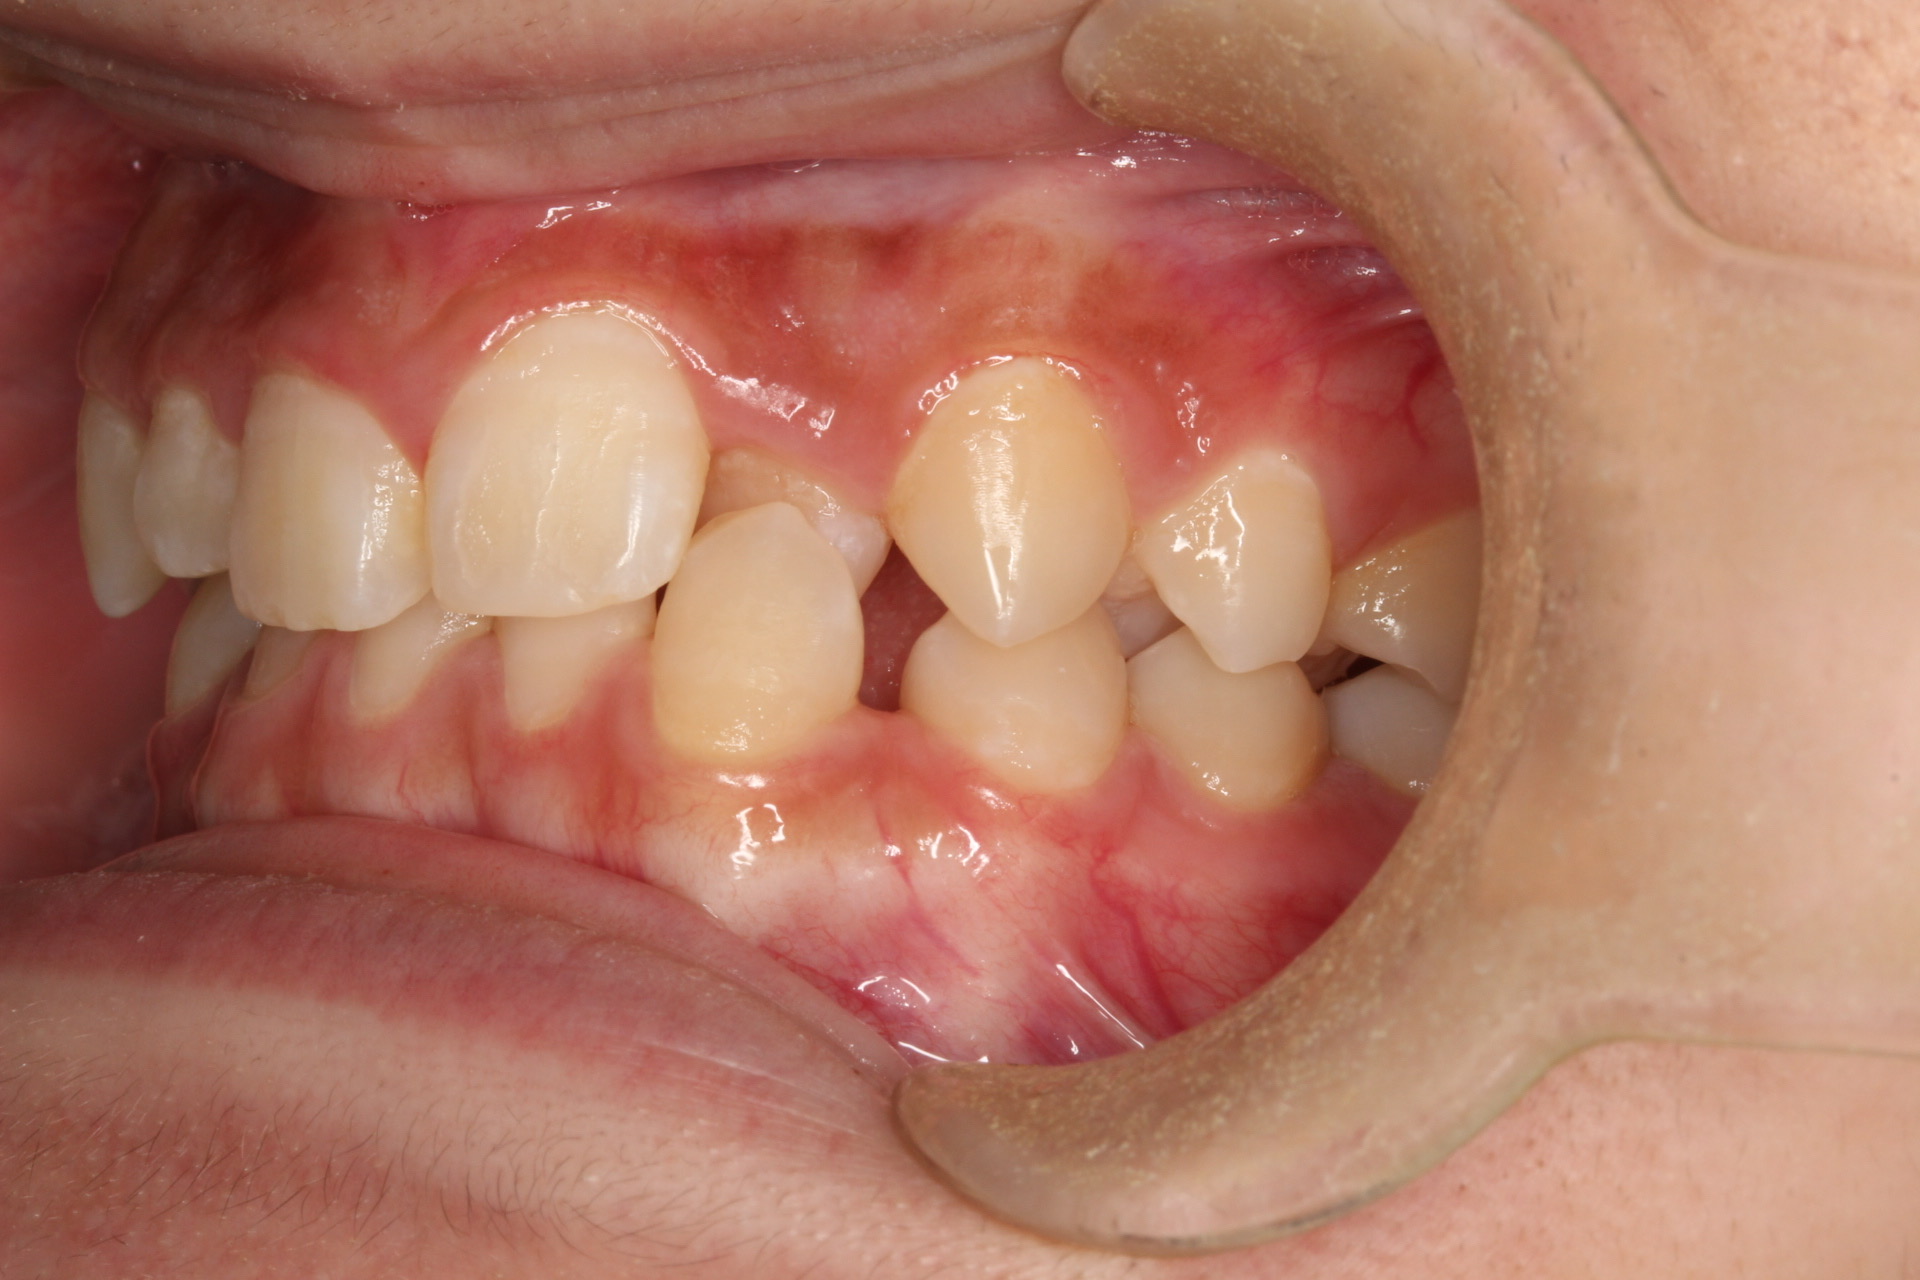

矯正術前:前歯部あおり

| 主訴 | 上の歯が1本だけ奥に引っ込んでいることが気になる |

| 治療内容 | 患者様は、上の歯が1本だけ奥に引っ込んでいることを気にされており、矯正検査後Ⅱ級傾向の叢生と診断いたしました。ワイヤー矯正後に、インビザラインによる仕上げ矯正を行っております。 |